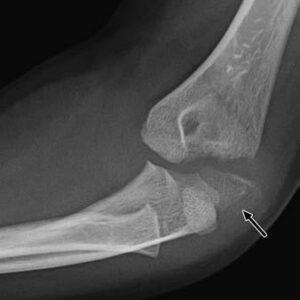

[toggle title=”Medial Epikondiler Kırıklar” state=”close”]

Çoğunlukla 10-14 yaş arası çocuklarda görülür.

Yaralanma direkt travma sonucu olabileceği gibi fleksör kas grubunun oluşturduğu avülsiyon sonucu ya da dirsek çıkığına sekonder de olabilir.

Medial epikondil kırıklarının yarısına yakınında eşlik eden dirsek çıkığı da görülür. Bu hastalarda dirsek redükte edildiğinde medial epikondil kırığı da redükte olur.

Kırık parçanın eklem içinde kalması nedeniyle redüksiyon yapılamayan durumlarda ya da kırığa eşlik eden ulnar sinir yaralanması varlığında cerrahi tedavi gerekir.